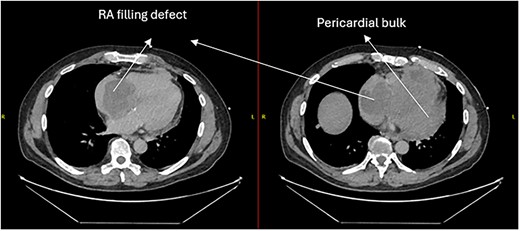

A 52-year-old gentleman was admitted to a district general hospital for shortness of breath causing type 1 respiratory failure with oxygen saturations of <90% despite high flow oxygen. His past medical history was unremarkable, and he was usually fit and well. A CT Pulmonary Angiogram (CTPA) was undertaken, which showed a heterogeneous oval-shaped lesion measuring 15 × 9 × 14 cm3 between the heart and the diaphragm, with a median attenuation of 35 HU and no enhancement during the arterial phase. Further solid lesions of 14 mm in the right lower lobe and 5 mm in the right upper lobe raised the suspicion of a primary cardiac sarcoma with pulmonary metastasis. This is shown in Fig. 1. Subsequent urgent CT staging (Fig. 2) was undertaken, which confirmed an indeterminate space occupying the inferior pericardial space, right atrial (RA) filling defect and anterior nodular pericardial thickening. No intra-abdominal or bone lesions were identified. An echocardiogram also confirmed these finding with the addition of no flow through the tricuspid valve (TV), as shown in Fig. 3.

CTPA showing oval-shaped heterogenous lesion as well as RA filling defect.

CT thorax-abdomen pelvis, depicting the RA filling defect as well as pericardial bulk.